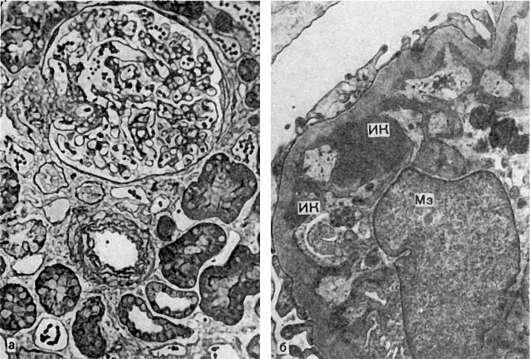

Механизм остро го диффузного гломерулонефрита